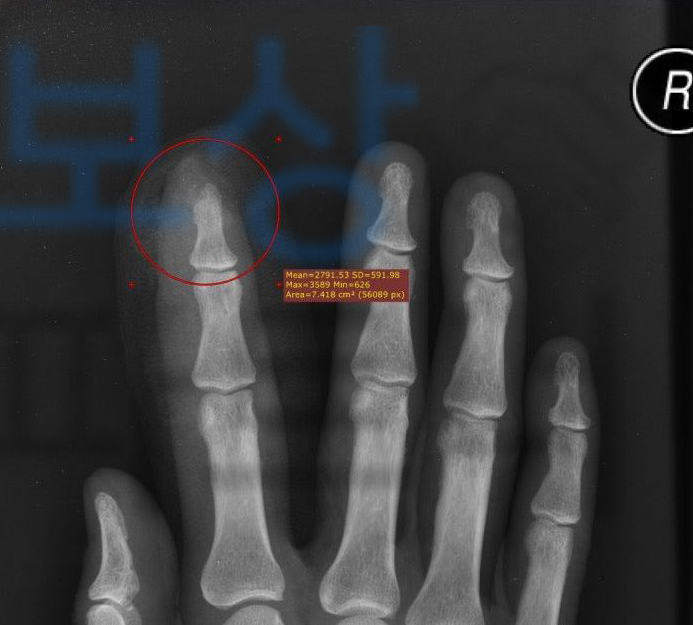

김@@님은 회사에서 일하시다가 컨베이어 벨트에 손가락이 끼는 사고가 발생했고 근처 병원에 내원하여 응급처치 후 수지 전문병원으로 이송되었습니다. 김@@님의 손가락의 골편이 이미 떨어져 나갔기에 핀 고정술보다는 봉합술을 위주로 시행했고

변연 절제술, 창상봉합술, 무지구피판술,

**피판분리술 **등의 수술을 받으셨습니다. 손가락골절 되었지만 핀 고정하지 않고 봉합술만 하였는데도 장해에 해당될까요?